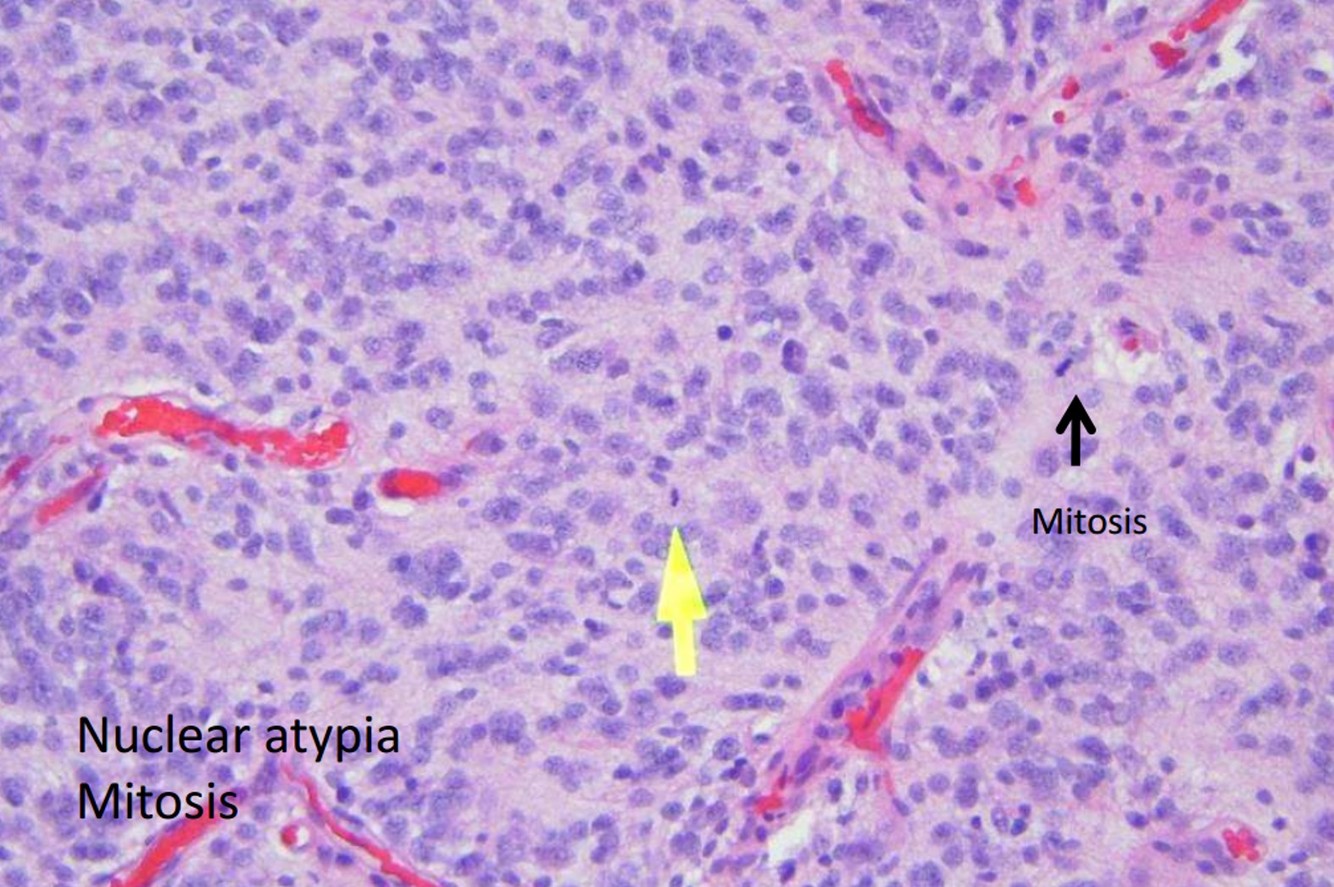

- Anaplastic astrocytoma

- WHO Grade III:

- WHO Grade III: anaplastic astrocytoma

- Anaplastic astrocytoma: 45 y/o